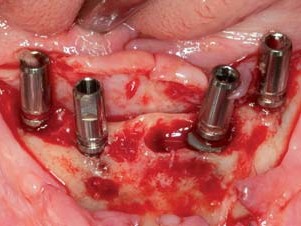

Individuelle Abutments, Patrize und Matrize bei Konusprothesen

Nach viermonatiger Einheilzeit wurden die Implantate bei reizlosen Weichgewebsverhältnissen freigelegt, Ober- wie Unterkiefer geschlossen und indexiert abgeformt und die Situation mit Zahnfleischmaske auf das Meistermodell übertragen (Abb. 11–14). Die Wahl des geeigneten Abutments richtete sich nach der Dicke der periimplantären Mukosa, wie sie in der Zahnfleischmaske widergespiegelt ist, und der Position der Implantate im Verhältnis zu der ästhetischen Position aus der Wachsaufstellung. Klebebasen waren aufgrund der dünnen periimplantär-mukosalen Verhältnisse ungeeignet. Einteilige Abutments aus Zirkonoxid schieden wegen des Belastungsaspektes im Seitenzahnbereich aus. Die Ästhetik von titannitridbeschichteten Titanabutments kommt bei Teleskopprothesen nicht zur Geltung. Daher waren individuelle Titanabutments die erste Wahl. Nach einer Ästhetikeinprobe wurden die individuellen Abutments auf Basis der gescannten Ober- und Unterkiefermodelle bei ATLANTIS gestaltet und angefertigt. Zur Beschleunigung des Produktionsprozesses wurden die Modelle mithilfe des für ANKYLOS passenden ATLANTIS FLO (Feature Locating Object, DENTSPLYImplants, Mannheim) im Labor gescannt (3Shape D700, Kopenhagen) und die Daten digital übermittelt.